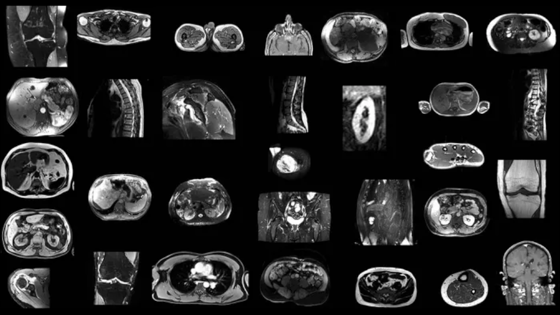

Новая модель искусственного интеллекта эффективно анализирует МРТ-снимки

Ученые разработали надежную модель искусственного интеллекта, которая автоматически выделяет основные анатомические структуры на изображениях МРТ независимо от последовательности сканирования. Модель показала лучшие результаты по сравнению с другими общедоступными инструментами. При анализе 13 анатомических структур модель оказалась на 49,6% эффективнее аналогов. Новая разработка поможет сократить время и усилия, затрачиваемые на ручную обработку изображений, а также уменьшить количество ошибок. Результаты исследования опубликованы в журнале Radiology.

Ученые разработали и обучили модель искусственного интеллекта TotalSegmentator MRI проводить независимую от последовательности снимков сегментацию основных анатомических структур, используя случайную выборку данных из 616 МРТ и 527 КТ-исследований. Обучающий набор включал снимки с сегментацией 80 анатомических структур, обычно используемых для измерения объема, характеристики заболевания и планирования хирургического вмешательства.

Модель TotalSegmentator MRI продемонстрировала коэффициент Дайса 0,839 на внутреннем тестовом наборе изображений МРТ, что указывает на хорошую производительность по 80 анатомическим структурам. В сравнении с двумя другими общедоступными моделями сегментации разработка достигла коэффициента Дайса 0,862 для 40 анатомических структур (против 0,759) и 0,838 для 13 анатомических структур (против 0,560).